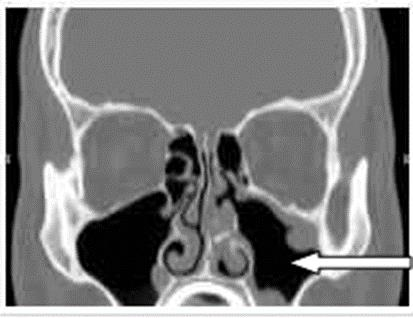

Na zamieszczonym obrazie TK strzałką zaznaczono zatokę

A. szczękową w przekroju czołowym.

B. czołową w przekroju czołowym.

C. szczękową w przekroju strzałkowym.

D. czołową w przekroju strzałkowym.